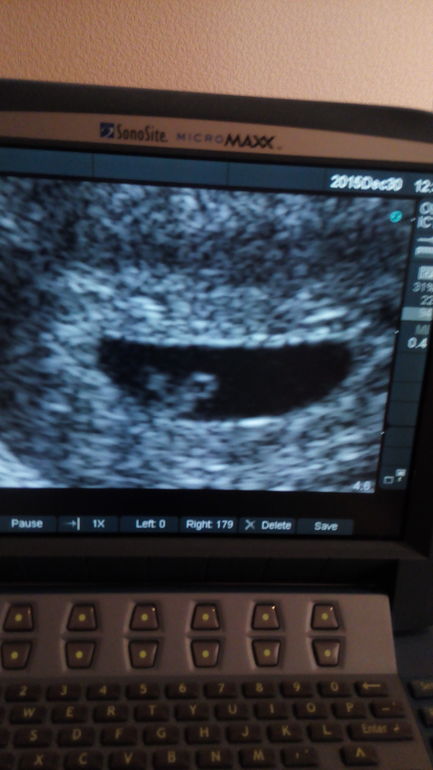

Ещё УЗИ!!!

О хорошемСегодня была ещё раз на УЗИ. Теперь спокойна и счастлива. КТР 7 сердцебиение + . сказала узистка все соответствует сроку. 6 недель 5 дней.

Да, в 6 недель вообще не видно было эмбриона, по этому и делала ещё раз через 5 дней. И уже такой малыш 7 мм